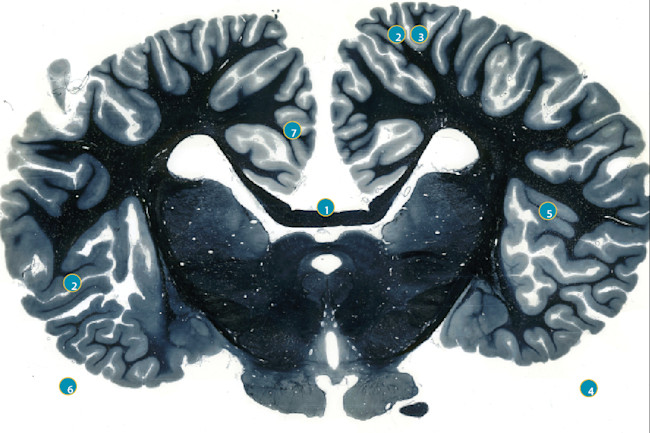

The implantation of electrodes in the brain has been used by clinicians since the 1930s, most notably by neurosurgeon Wilder Penfield, who initially used this method to treat patients with epilepsy. Ride on shooting star 10. Tours ne view full version of pwcom best books authors publishers weekly advertisement quirk brain.